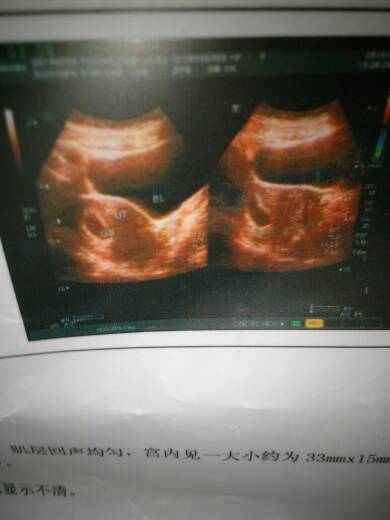

子宫前位,宫体形态饱满,肌层回声均匀,宫内见一大小约为33mm x 15mm无回声囊,囊内可见细小

子宫前位,宫体形态饱满,肌层回声均匀,宫内见一大小约为33mm x 15mm无回声囊,囊内可见细小胚芽及原始心管搏动,并见卵黄囊回声。这是B超描述正常吗????两个月检查的!!!